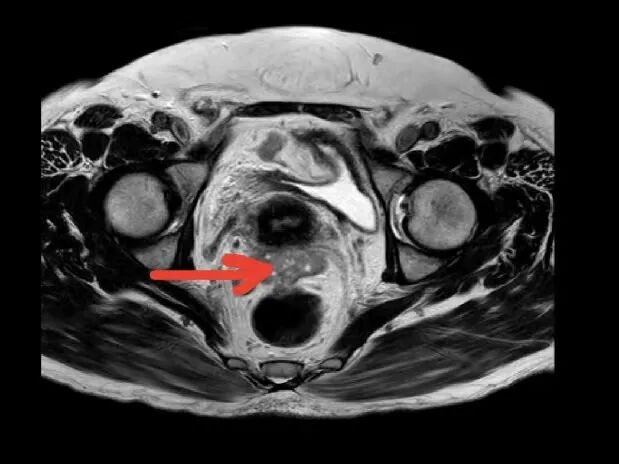

65岁的陈女士,因反复口干、多尿多饮、伴疲劳乏力,偶有胸闷,监测空腹指尖血糖超过11mmol/L,来我院内分泌科住院治疗,入院后完善相关检查,其中在子宫双附件彩超筛查中发现子宫上方见一类圆形低回声团,大小约37x32x37mm,边界不清,内部回声不均匀,这意味着不排除肿瘤可能。在积极控制血糖的同时,进一步完善了盆腔MR增强等针对性检查,结果提示:双侧附件区、

子宫直肠陷凹

及子宫周围多发结节状、团块状异常信号影,考虑附件区恶性肿瘤, 伴子宫直肠陷凹及子宫多发转移。内分泌科主任颜文盛考虑到该患者病情复杂,立即申请妇科会诊。经过妇科团队会诊,近期可能需要专科手术干预治疗,他与家属充分沟通后,家属果断选择转入广州市花都区人民医院妇科。

盆腔MR(红色箭头为病灶)